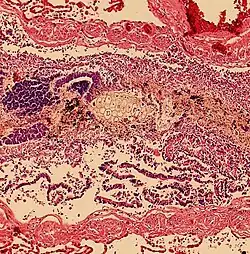

Aspiration pneumonia is when bacteria is carried into the respiratory tract via aspiration and subsequently causes an infection of the lung. Any substance or object that is aspirated into the airway has the potential of carrying infectious agents with it into the respiratory tract. It primarily affects older adults and can be especially severe in patients with learning disabilities, or disorders of abnormal swallowing.[14]

Aspiration pneumonitis

Aspiration pneumonitis (Mendelson's syndrome) is chemical injury of lung tissue secondary to aspiration of regurgitated gastric acid.[15] The syndrome was first described among pregnant patients[16] after the administration of anesthesia, though it can occur in any scenario where gastric contents are aspirated.[17]